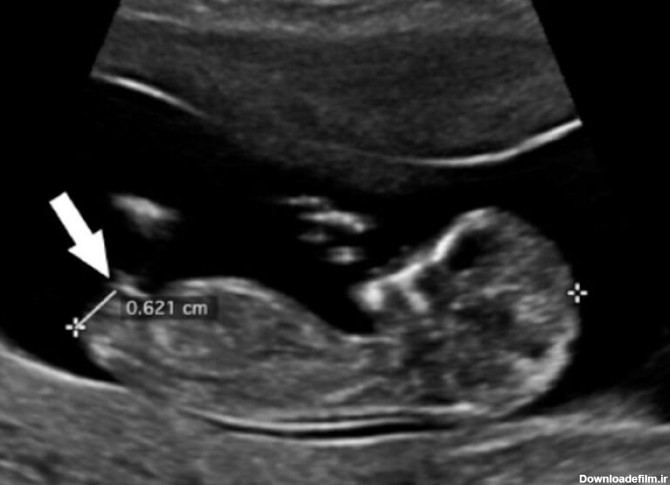

عکس جنین دختر و پسر در سونوگرافی از نظر نوع و شکل آلت تناسلی با یکدیگر اختلاف دارد. در پسرها شامل بیبضه و در دختر ها شامل لبیا است.

عکس جنین پسر در سونوگرافی فقط از نظر اندام تناسلی با عکس جنین دختر متفاوت است که تصویر آن را در این متن خواهید دید.